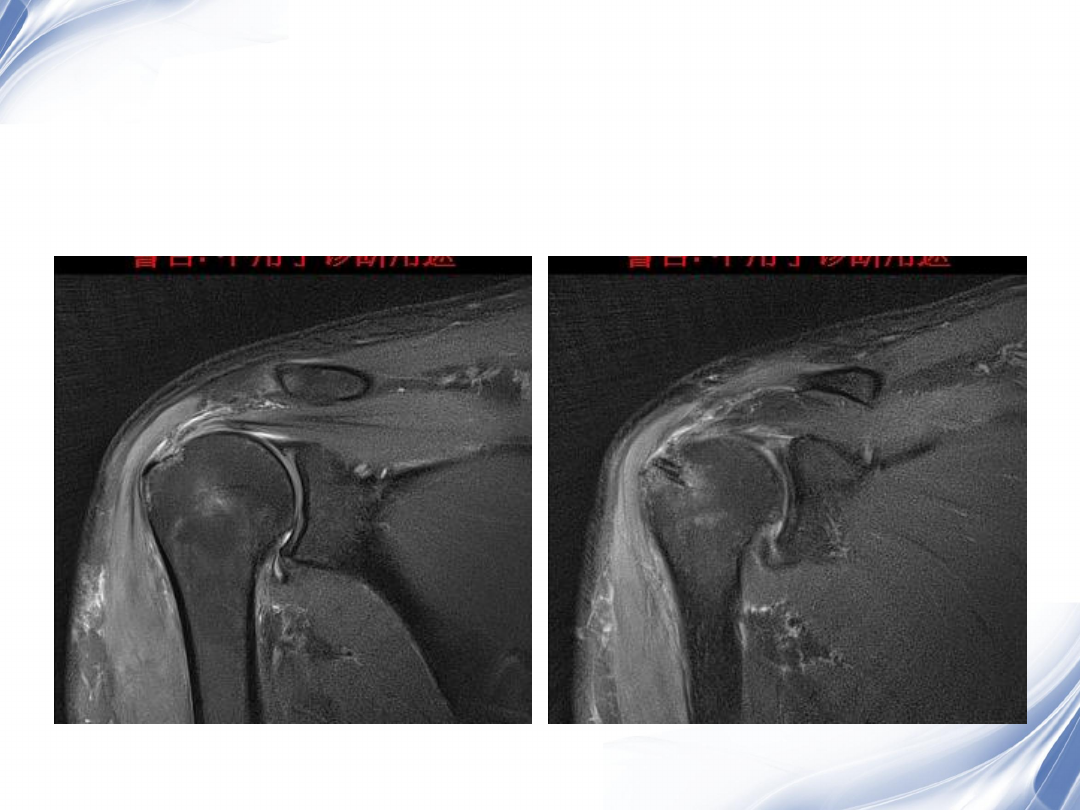

斜冠状位(临床最常用)

T2

T1

31

斜矢状位

冈上肌出口,肩袖诊断不如

斜冠状位

冈上肌及肌腹脂肪浸润成度

,评估手术与否

32